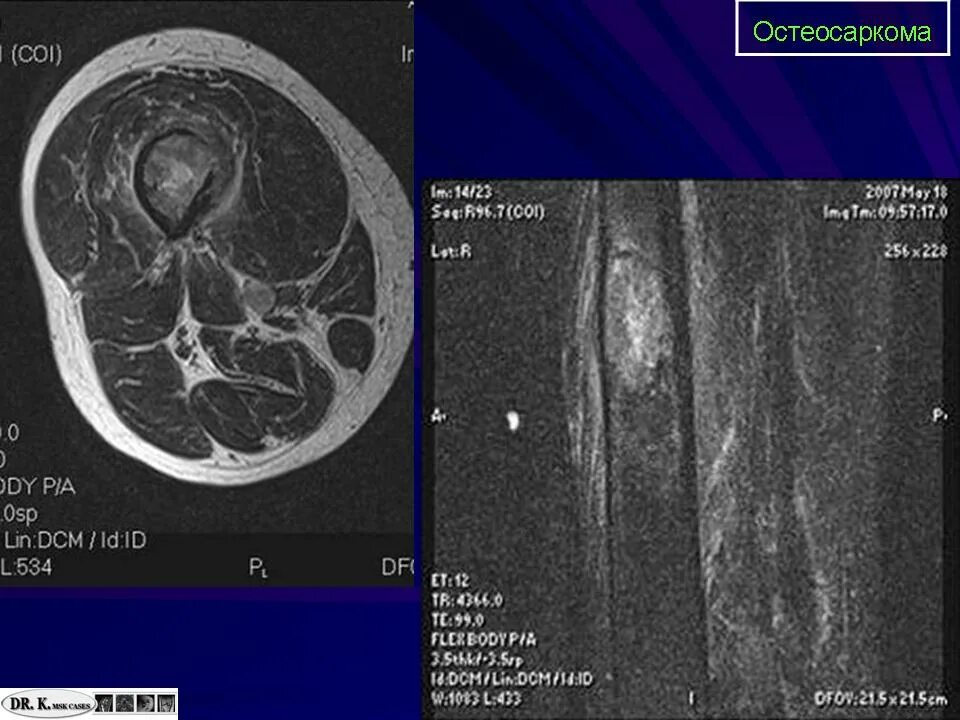

Саркома мрт